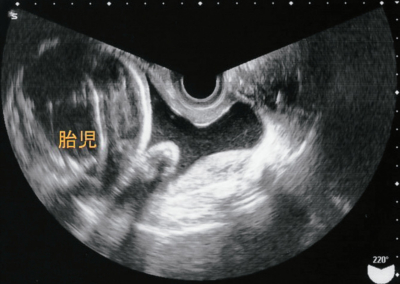

来院時の腟鏡診で淡血性の帯下を少量認めた。内診で子宮口は閉鎖していた。腹部超音波検査では胎児は頭位で形態異常はなく、推定体重は 1,850 g、胎盤は子宮底部に付着し、羊水指数<AFI>は 18.0 cm であった。胎児心拍数陣痛図及び経腟超音波像を別に示す。